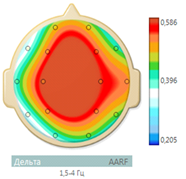

On an EEG, after the first course of stem cell administration, significantly decreased the amount of epileptic formal activity (Figure 5). The frequency of spikes in the left temporal region STI decreased from 30 to 2 per min, the frequency of bilateral synchronization discharges of acute alpha waves remained at the level of 1-2 in minutes. At a frequency of alpha rhythm of 10.5 Hz, normalization occurred of its frequency-spatial structure, but the structure maximum mean coherence values are still was presented in the form of a triangle, which indicated the presence of an active epileptic process.

On the EEG, after the second course of stem cell administration, paroxysmal activity was not registered (Figure 6).

On the EEG, a disorganized alpha rhythm was maintained with a peak frequency of 12.5 Hz with a diffuse increase in beta activity. Its frequency-spatial structure is largely normalized. A reduction in the pathological structure of the maximum values of mean coherence in the form of a triangle was also noted (Figure 7 & 8).

Figure 8 Reduction of the pathological structure of coherence in the form of an "epileptic triangle" (the maximum values of the average coherence are presented in the form of a diamond).